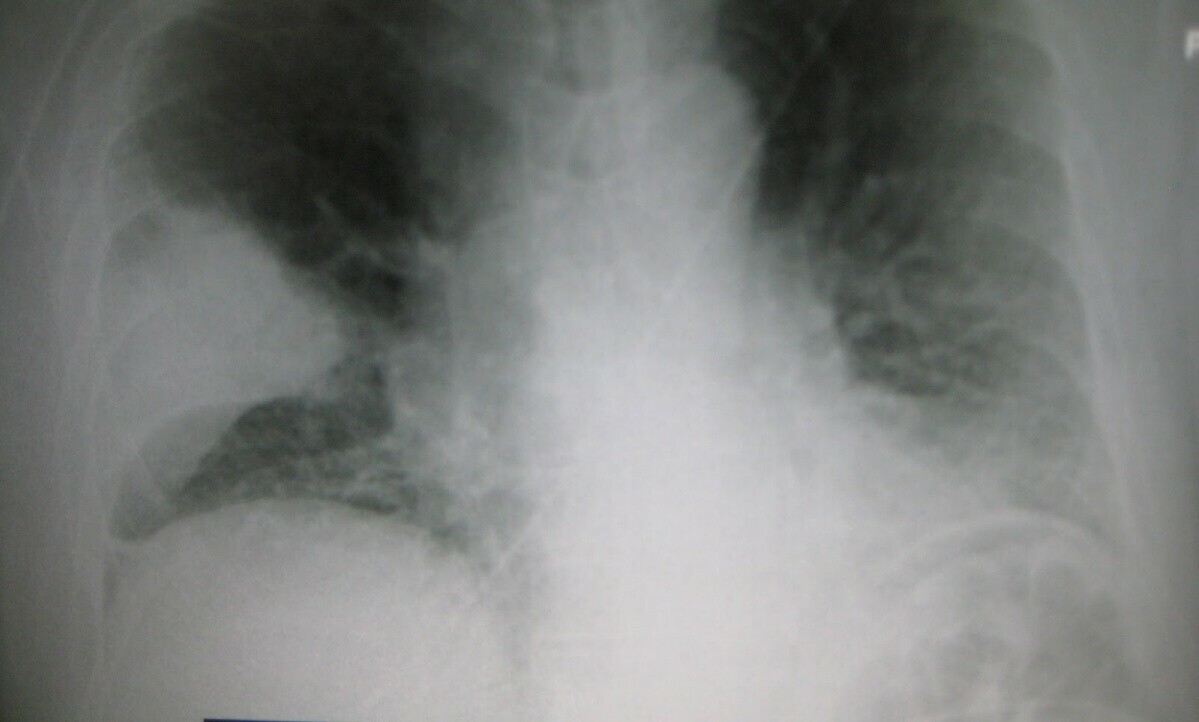

پنجاب میں نمونیا کے باعث مزید 5 بچے چل بسے

سردی کی شدت میں کمی کے باوجود نمونیہ سے بچوں کے جان سے جانے کا سلسلہ تھم نہ سکا